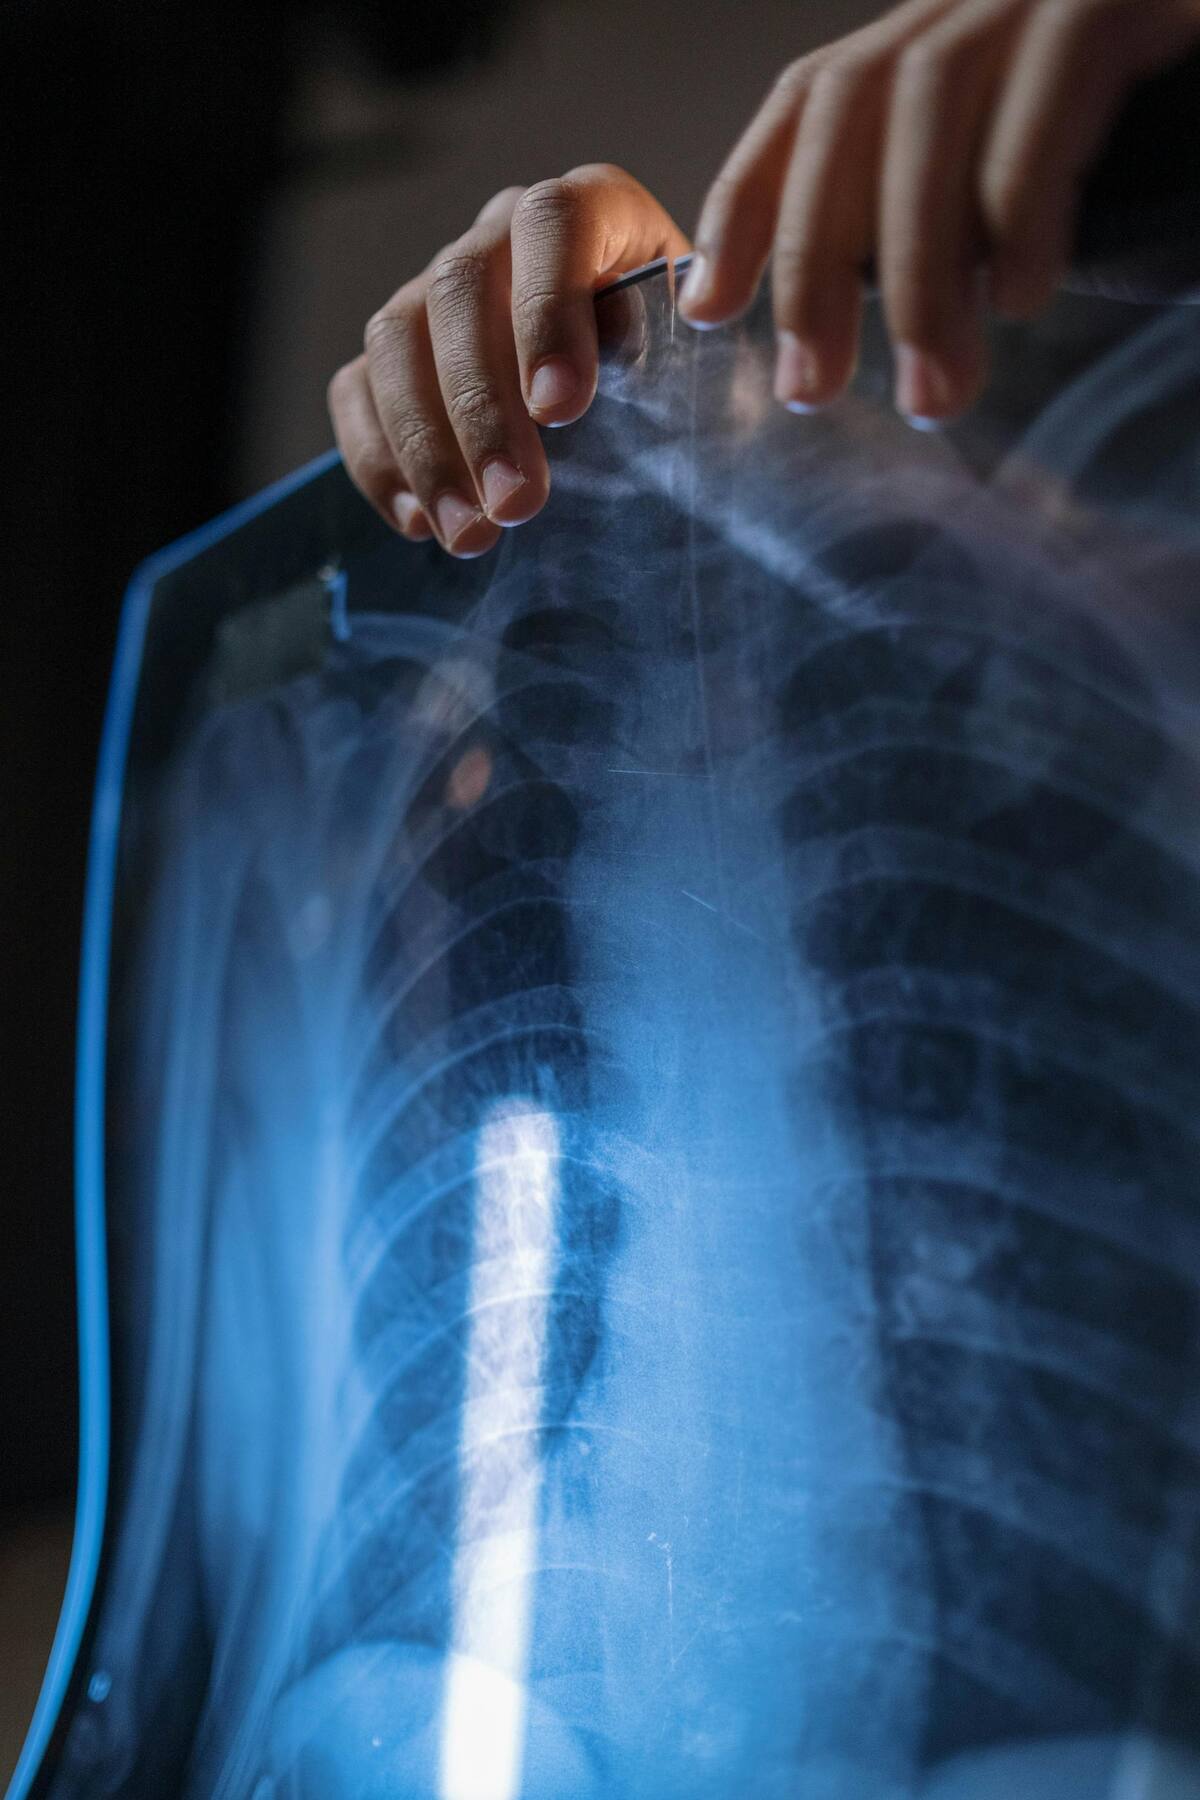

Tras haber ingerido las monedas y los imanes, durante los últimos 20 días, el sujeto comenzó a presentar síntomas como vómito y dolores estomacales, lo que lo obligó a dirigirse al hospital, donde decidieron realizarle una radiografía abdominal, la cual reveló anomalías.

Al revisar los rayos x, los médicos realizaron una tomografía computarizada que reveló una obstrucción intestinal, por lo que se debió realizar una cirugía, extrayendo del estómago del paciente 37 imanes con forma de estrella, bala, triángulo y corazón, y 39 monedas de una, dos y cinco rupias, según el medio indio The Financial Express.